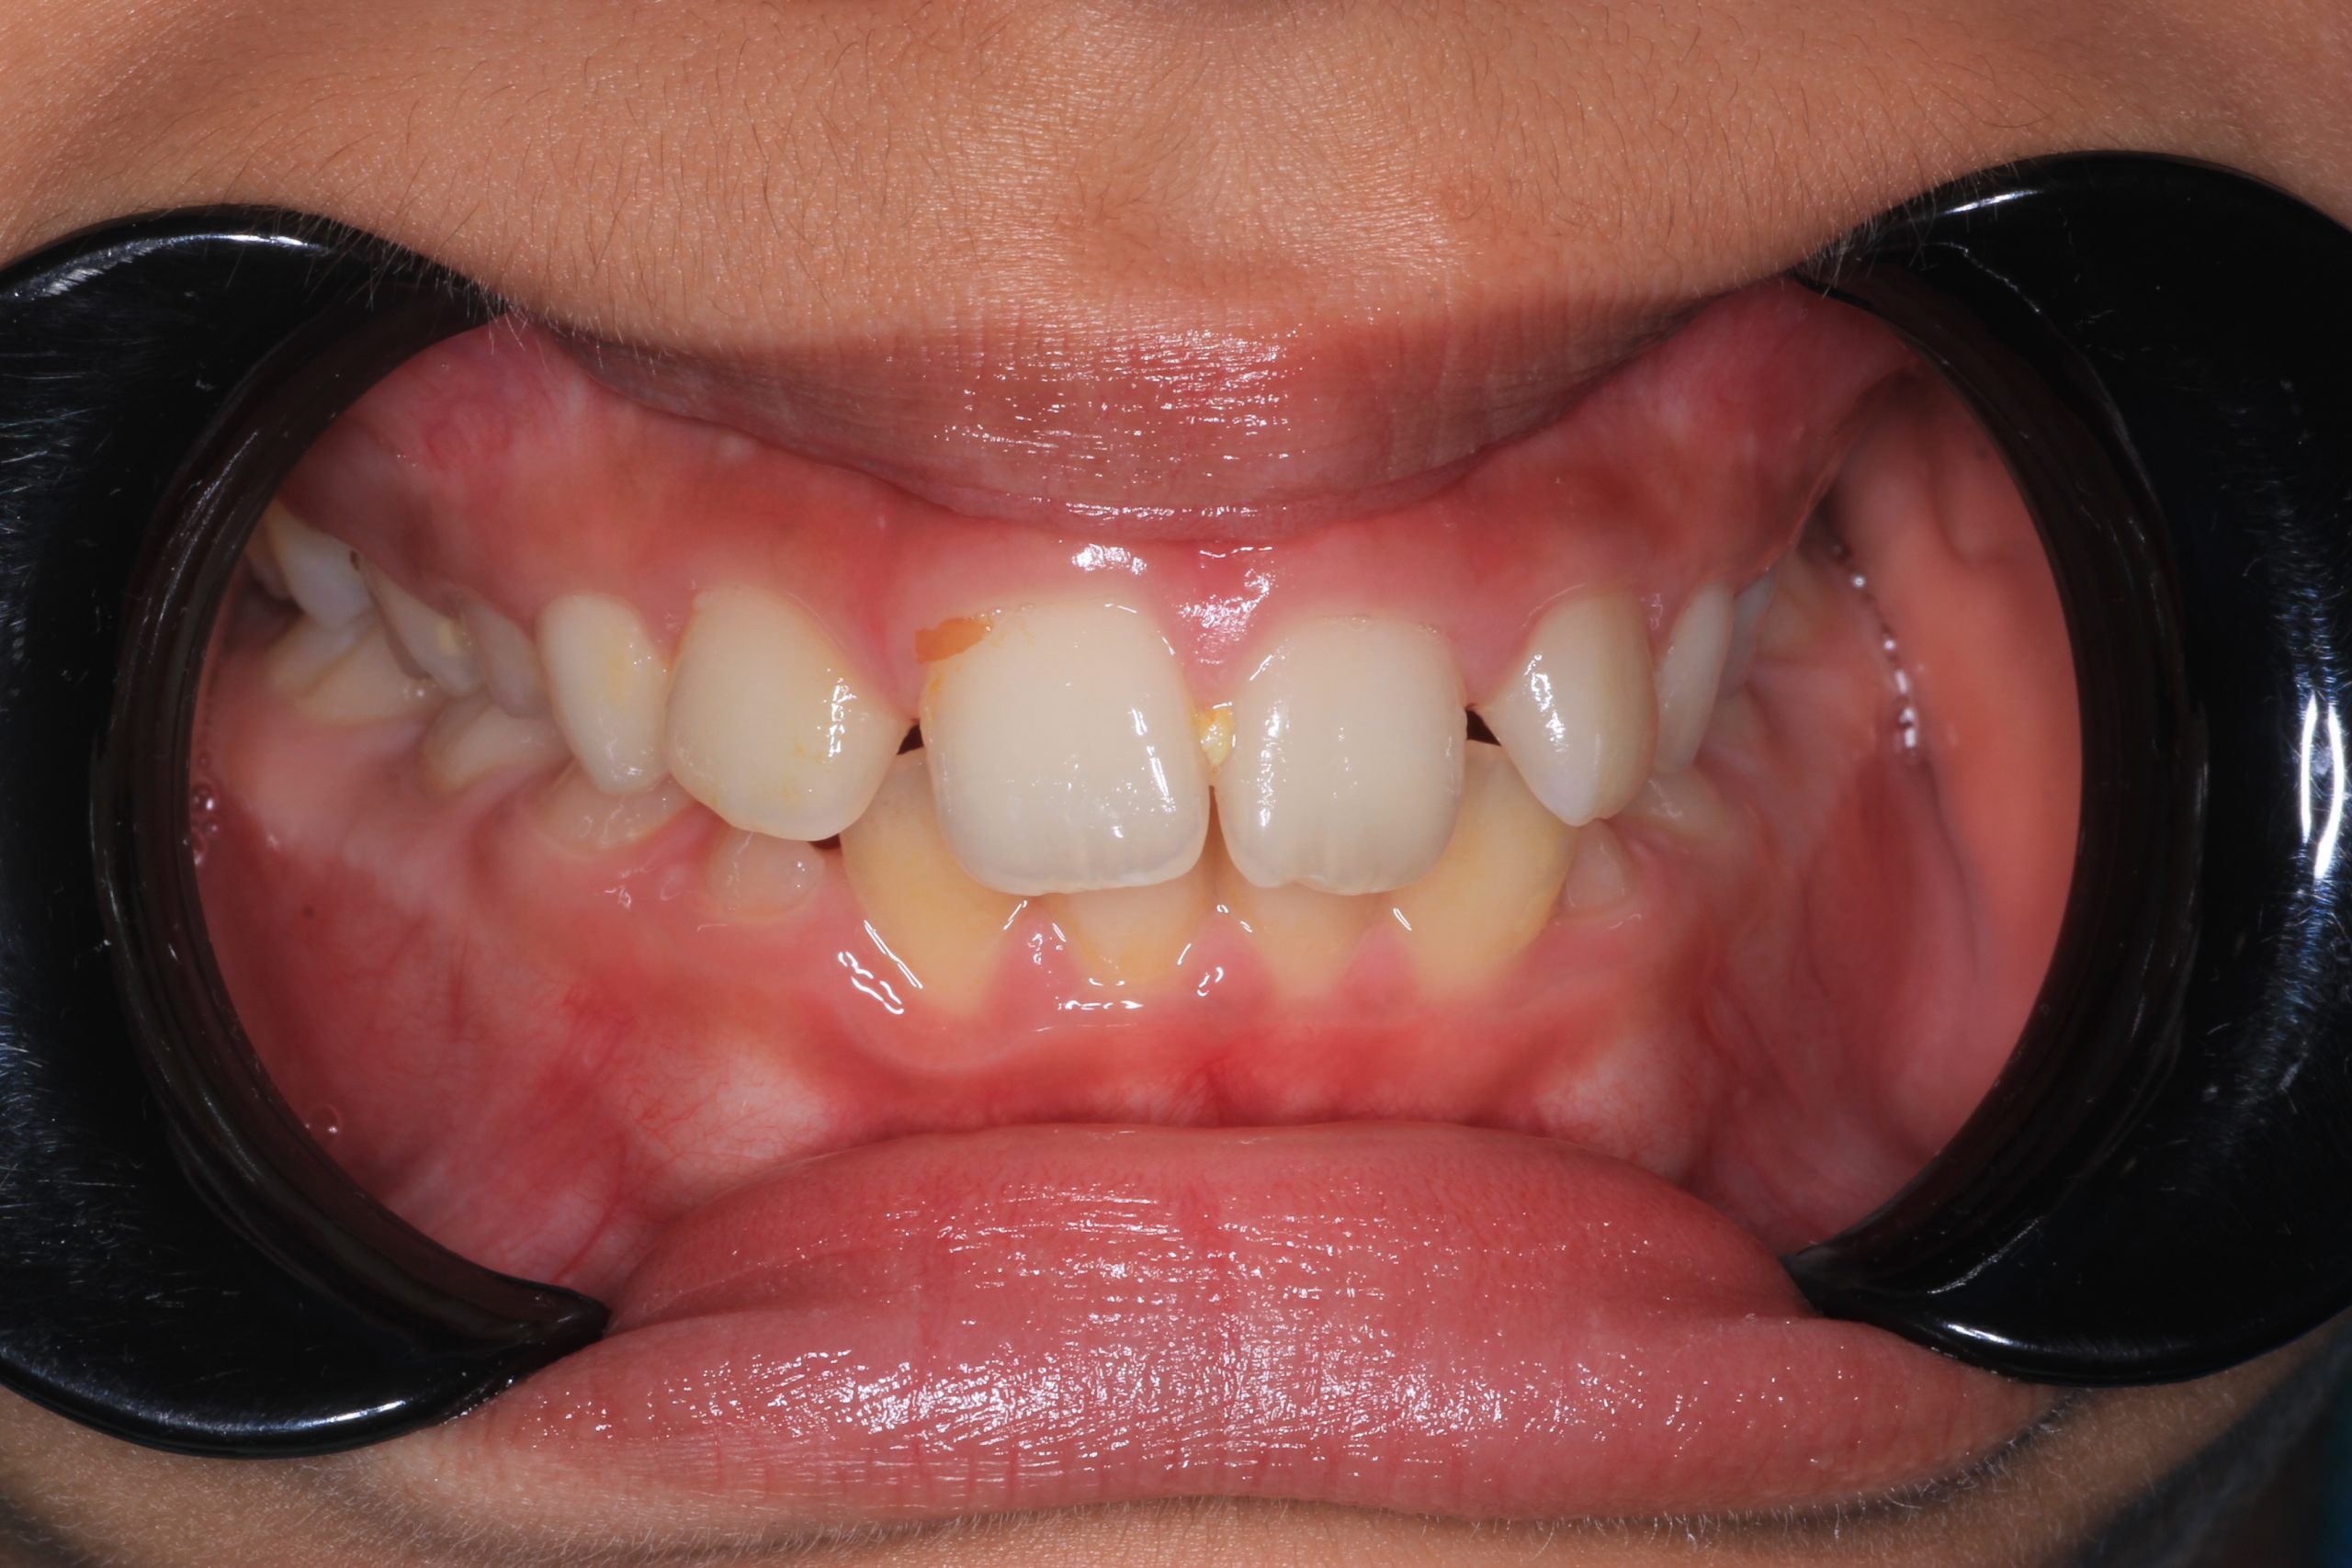

We examine the condition of teeth, gums, and bite. - Plaque Disclosure with Special Indicators

Areas that weren’t cleaned well appear purple. The darker the shade, the older the plaque. This helps both kids and parents understand where brushing needs to improve. - Brushing Training & Home Care Tools Selection